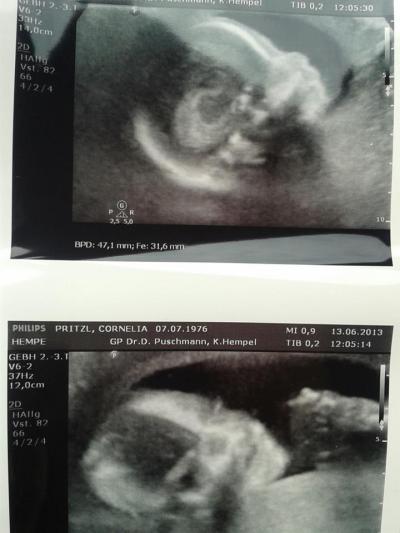

Hallo ich habe das Bildchen ganz vergessen euch zu zeigen das hole ich nun schnell nach!